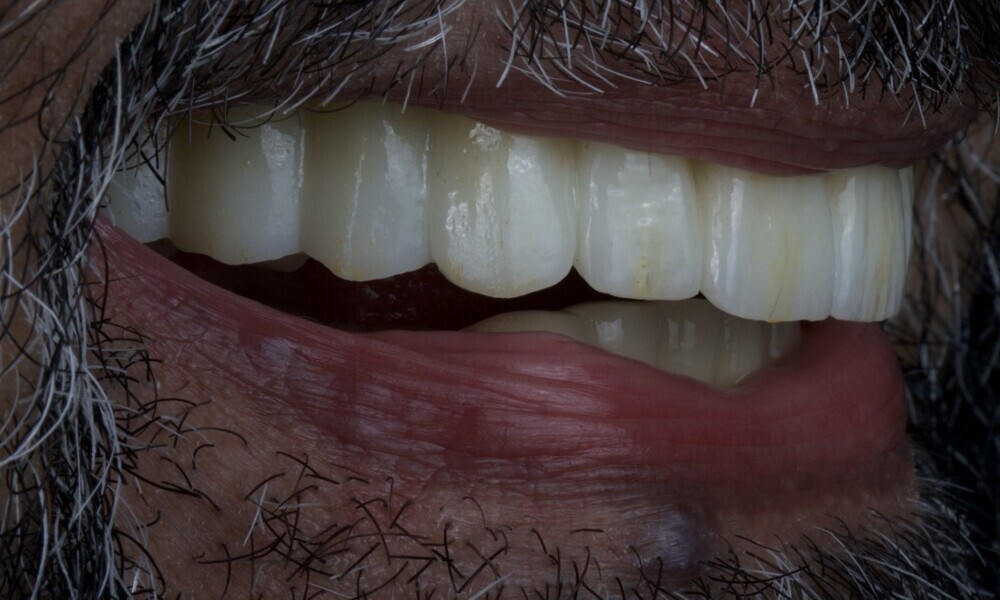

A generally healthy 65-year-old male patient who smoked ten cigarettes per day and reported no medications presented to our clinic seeking a maxillary fixed restoration to replace his existing removable partial denture. His primary goal was to achieve a natural-looking smile that closely mimicked the appearance of natural teeth in terms of shape, colour and alignment. Additionally, he desired the new restoration to be stable and free from movement, providing a secure fit that would enable him to chew food properly without discomfort or difficulty, improving his overall quality of life.

Extra-oral examination showed no significant abnormalities. The patient presented with a medium smile line (Figs. 1–3). The intra-oral examination revealed a fixed bridge spanning teeth #23–26 to which the removable metal partial denture attached (Fig. 4). Teeth #22–17 had been extracted a long time before, and the ridge in this region had healed. No plaque or inflammation was observed. The teeth exhibited mild to moderate attachment loss, but no endodontic or periodontic lesions or root fractures were observed (Figs. 5–8). Analysis of the panoramic radiograph indicated sufficient vertical and horizontal bone availability and adequate bone quality; therefore, there was no need for guided bone regeneration (Fig. 9). According to the International Team for Implantology’s SAC classification, the case was categorised as advanced to complex.

The delivery of the final prosthesis was then performed, and the aesthetics, occlusion and function were verified (Figs. 51–55). The panoramic control radiograph showed that all measurements were within expected ranges (Fig. 56).

At the 18-month follow-up after completing the treatment, an intra-oral, extra-oral and radiographic evaluation were performed. No pathologies were observed, and the results remained stable over time (Figs. 57–62). The patient expressed his satisfaction with the treatment outcomes, stating, “Seeing my new smile before starting the procedure was a game-changer. I was confident from the beginning that my final result would be as I had imagined.”